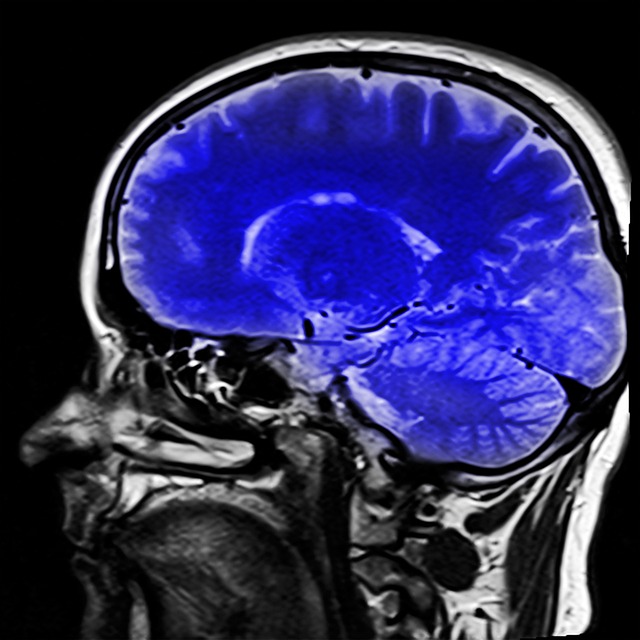

● 마이크로바이옴-뇌 영상 연구: 기능성 자기 공명 영상(fMRI) 및 양전자 방출 단층 촬영(PET)과 같은 신경 영상 기술의 발전을 통해 연구자들은 생체 내 장-뇌 축 상호 작용의 기초가 되는 신경 회로를 조사할 수 있습니다. 미생물군집 데이터를 뇌 영상 연구와 통합하면 장내 미생물군이 뇌 기능과 행동에 영향을 미치는 신경 메커니즘을 밝히고 정신 건강 장애에 대한 잠재적인 치료 목표에 대한 통찰력을 제공할 수 있습니다.